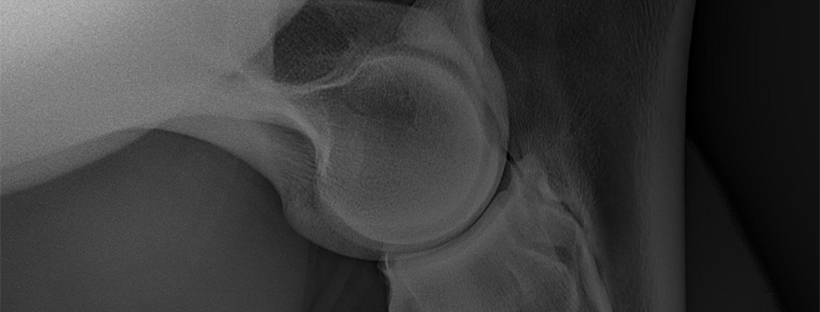

We’ve Got Lameness and Vet Bills A-Plenty | Ax Update

I think it is time that you all get an update on my beloved buffalo.

This has been the year of maladies for Ax—earlier this year he sliced his mouth open which resulted in some minor stressing, an unexpected (and perfectly timed) vet visit, and some time off, and now we are approaching week four of stall rest due to a mystery lameness that has my vets stumped.

Continue reading “We’ve Got Lameness and Vet Bills A-Plenty | Ax Update”